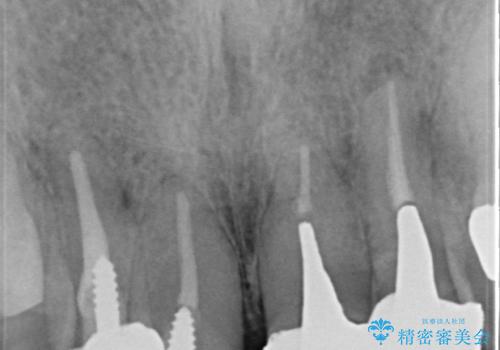

再根管治療後、オールセラミッククラウンによる補綴を行いました。

根管治療の注意事項(リスク・副作用など)

- 根管治療により類似の全ての症例の問題が解決するわけではなく、症例はあくまでも一例です

- 根管治療により痛みや腫れがひかない事や、術後に痛みや腫れが生じる事、治療によるファイル破折やパーフォレーションなどの偶発症、術後の歯根破折を生じる可能性もあります